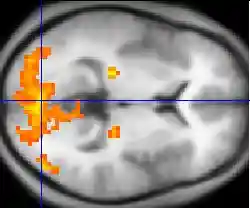

Neuroimaging has contributed to the identification of the neural components involved in drug reinstatement as well as drug-taking determinants such as the pharmokinetics, neurochemistry, and dose of the drug. The neuroimaging techniques used in non-human primates include positron emission tomography (PET), which uses radiolabeled ligand tracers to measure neurochemistry in vivo and single-photon emission computed tomography (SPECT).[3] Functional magnetic resonance imaging (fMRI) is widely used in human subjects because it has much higher resolution and eliminates exposure to radiation.[14]